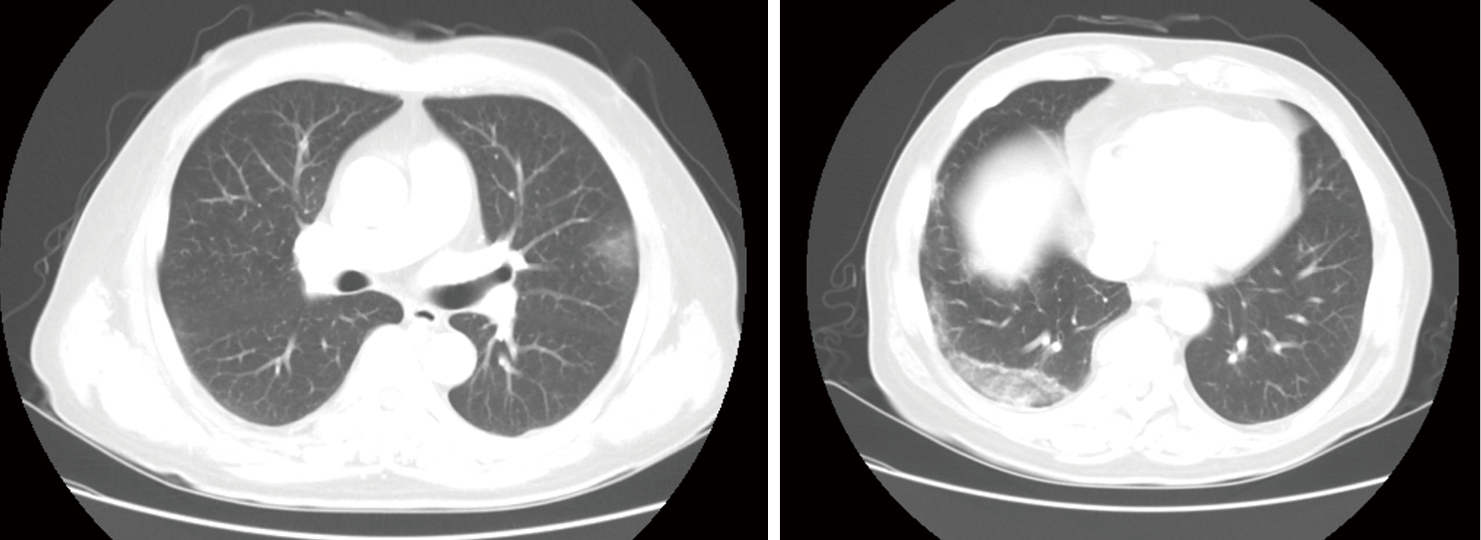

Time Course Of Lung Changes At Chest Ct During Recovery From Coronavirus Disease 2019 Covid 19 Radiology

Covid 19 Pneumonia What Has Ct Taught Us The Lancet Infectious Diseases